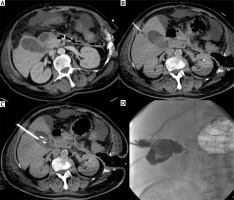

Photo 2

Incidental finding. Acute cholecystitis with enlargement of the gallbladder wall on the contrast medium enhanced CT examination (A). Cholecystostomy was indicated due to septic status related to necrotizing pancreatitis and performed using local anesthesia (B) and the transhepatic approach (C). Seven days after the intervention, routine cholecysto-cholangiography through the inserted drain was performed and revealed the communication with the hepatic vein (D)